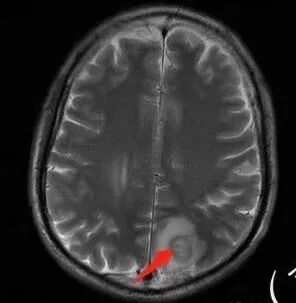

脑内右侧顶叶病灶与其它脑内病灶不一致,壁弥散受限,内容物弥散低信号,转移瘤不能排除,其它脑内病灶支持脑脓肿

肺内病灶符合脓肿,颅内病灶几个表现不一样,多数脓腔弥散受限,壁不受限制,但有一个表现跟其他不同,内部不受限,壁弥散受限

多数薄壁,脓腔弥散受限是典型脑脓肿;右侧额叶的厚壁,壁受限,表现跟其他完全不一样,很是疑惑

颅内部分病灶是环形受限,中心没有受限,不支持脓肿

脑部病灶DWI受限,脓肿,中间也有受限,DWI第一,第二张图都是中间受限,第三,四是周围受限

今天这个颅脑病灶需要转移和脓肿鉴别,转移和脓肿都可以这样环形强化,但是脓肿是中心弥散受限,脓肿壁弥散不受限,转移和脓肿弥散正好相反,转移是环壁弥散受限,中心坏死区弥散不受限。

DWI值对鉴别脑脓肿与囊性脑转移瘤有重要意义。包膜期脑脓肿其内容物主要为炎症细胞、微生物及蛋白质,其黏稠度相对较高,水分子弥散受到限制,DWI表现为均匀高信号。转移瘤囊变区主要以浆液性坏死物为主,其黏稠度相对较低,水分子扩散速度相对较快,DWI表现为低信号

脑脓肿和囊性脑转移瘤的鉴别点就是粘液(结合水)浆液(自由水)的鉴别

下图是例举其他病例: